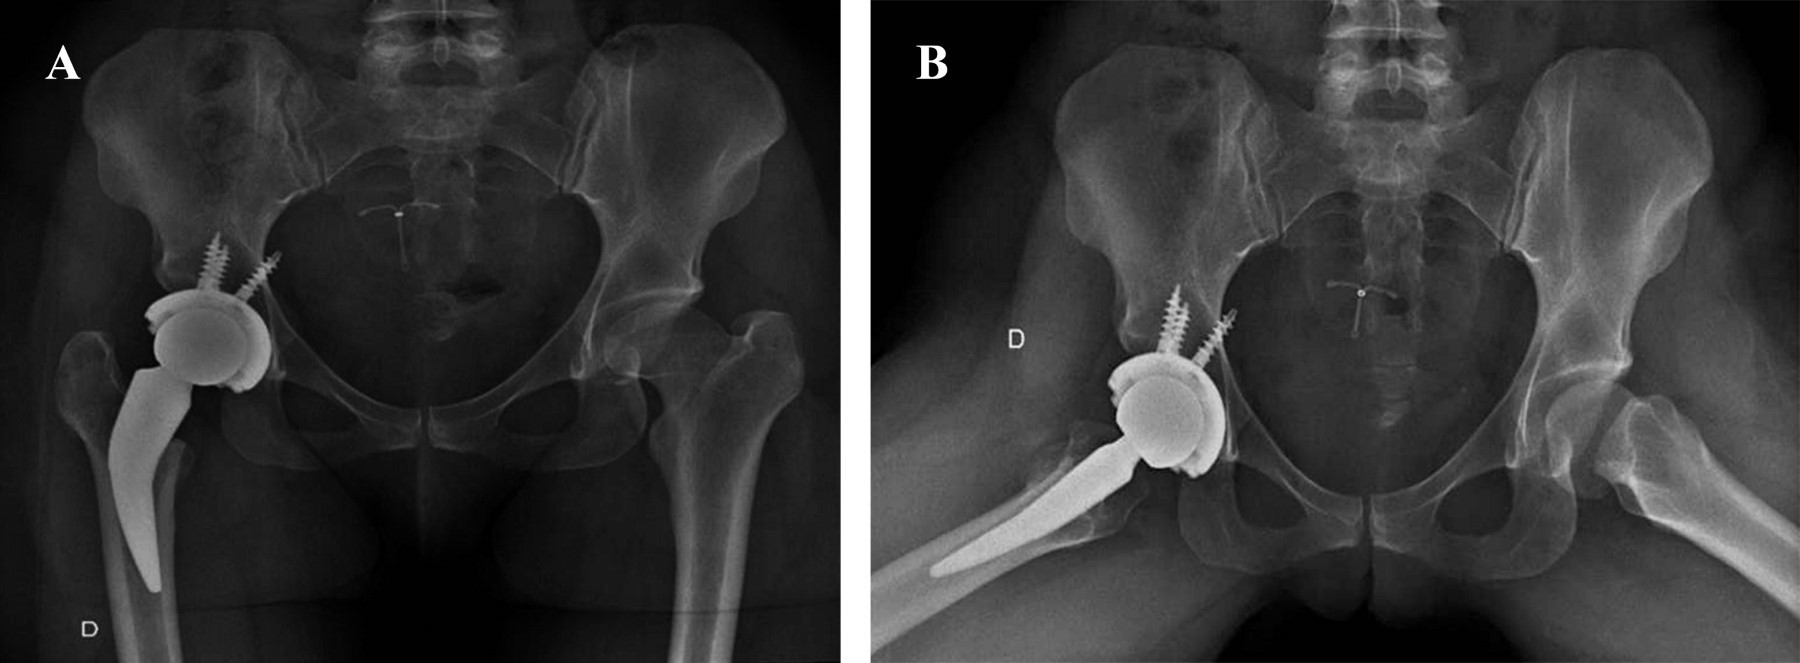

Las secuencias están ilustradas en las Figuras 1, 2, 3, 4, 5, 6 y 7.

EVALUACIÓN RADIOGRÁFICA

La anteversión acetabular tuvo un promedio de 10° (IQR 0°-15°), no observándose componentes acetabulares retroversos. El ángulo de inclinación tuvo una mediana de 43° (rango intercuartílico [RIC]: 38° a 51°). En dos (9.9%) pacientes se detectaron líneas radiolúcidas sin progresión o significancia clínica; el resto de los sujetos presentaron cinco de los signos radiográficos de Moore para osteointegración del cotilo. En 20 pacientes (90.1% de la serie), la medición postoperatoria de la longitud de los miembros no encontró discrepancia entre el operado y el contralateral, en un caso se presentó una hipermetría menor a 0.5 cm y una hipermetría entre 0.5 a 1 cm. En ningún caso hubo disconformidad con el resultado funcional. Se detectó la aparición de calcificaciones heterotópicas de tipo 1 (clasificación de Brooker) en dos casos, sin ninguna relevancia clínica.

Figura 1

Figura 2